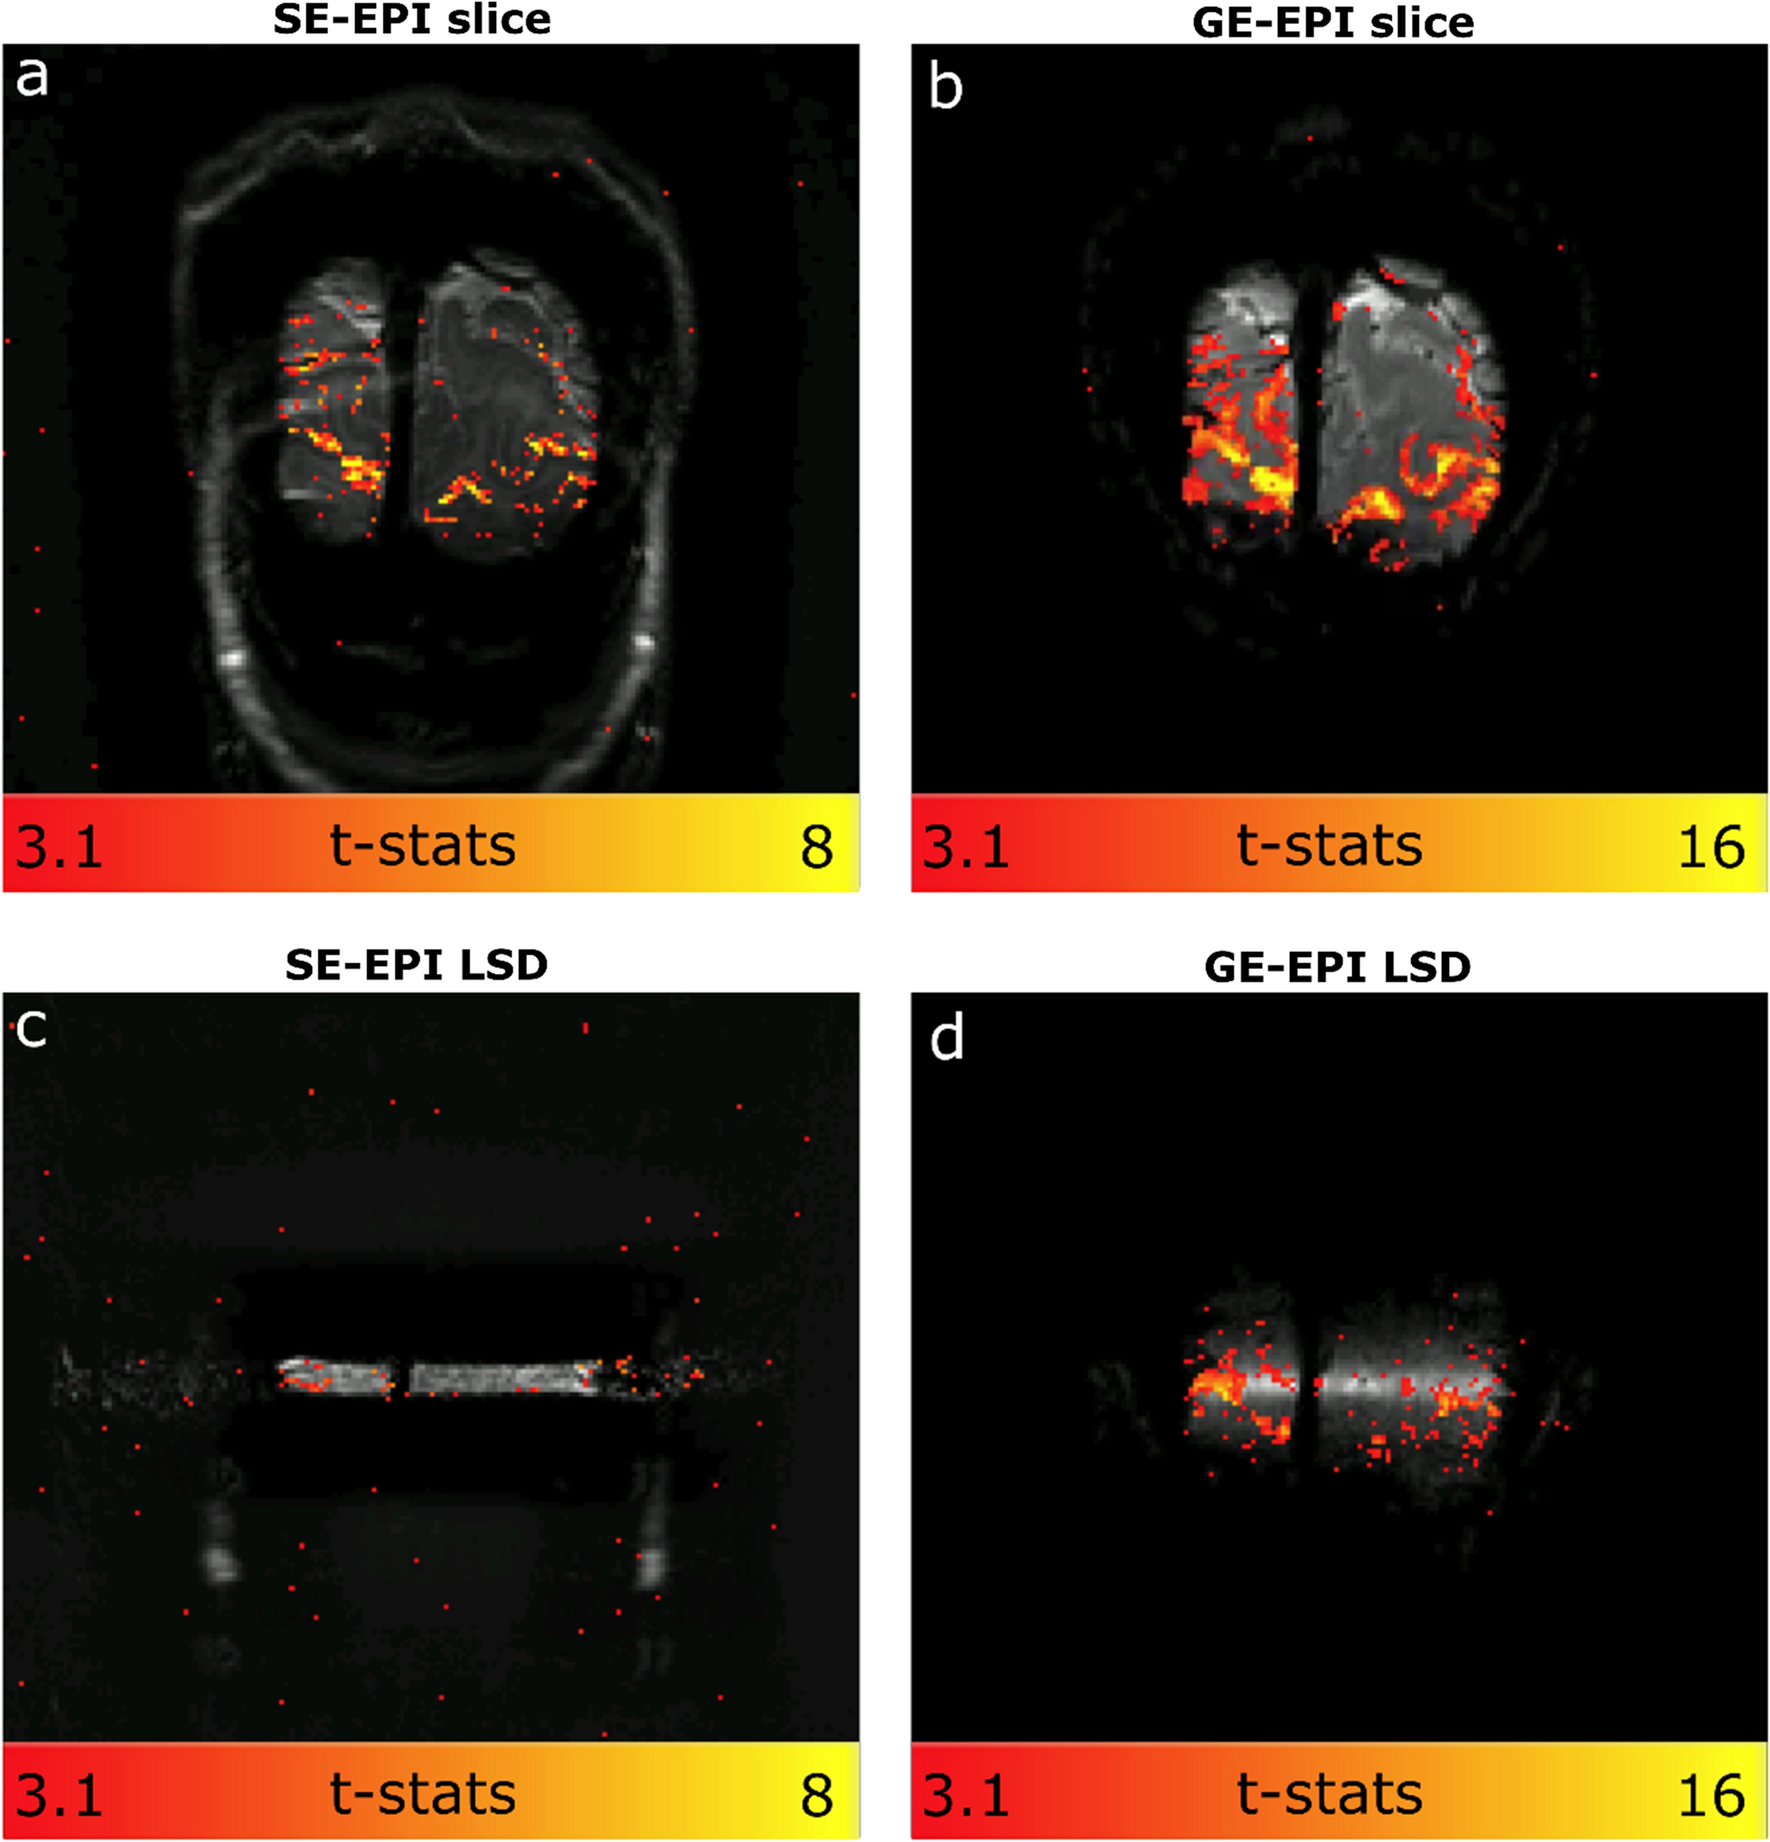

To investigate the sensitivity differences between the SELINE and GELINE protocols, independent from the line formation, we compared them in a limited-resolution image format as well, for both the slices and LSD images. Figure 5 shows the activation maps of the SE and GE-EPI slices and the accompanying functional LSD images. The SE-EPI showed solid but lower functional responses than GE-EPI. All functional responses were well within the gray matter areas in both SE-EPI and GE-EPI slice acquisitions. Note the different scales for GE-EPI and SE-EPI t-stats. The difference in functional sensitivity between SE-EPI and GE-EPI appeared to be larger in the LSD images (Fig. 5c and d). LSD functional images confirmed good line selection in SELINE but also highlighted the limited available functional signal in SELINE. Note that these voxels were larger than those used in the SELINE and GELINE acquisitions.

Fig. 5

a t-stats for SE-EPI slice acquisition, b GE-EPI slice acquisition c SE LSD image acquisition and d GE LSD image. The spatial resolution is 1.5 mm isotropic in all four acquisitions

Regarding the BOLD activation, smaller responses are expected in SE-BOLD weighted data [16]. Much work is undertaken to improve SE-based acquisition for functional imaging [16, 24, 2628]. Here, we used a single-echo acquisition. We could not detect significant task-driven activation in the SELINE, while GELINE consistently showed clear activation patterns in the visual cortex (on average across participants, t-stats were 3.9 times higher for 1 run of GELINE compared to SELINE). In the image-based comparison presented in Fig. 5, SE-EPI images have clearly defined functional responses located within the gray matter, though at lower t-stats values than GE-EPI. Functional activation is barely detectable in the SE-LSD images, while a clear activation is observed in the corresponding GE-EPI LSD functional images. This difference suggests that there is an additional loss in sensitivity in SE-EPI when generating a line rather than exciting and refocusing an entire slice, possible due to the small size of the target line. The data in Fig. 5 is drawn from a single individual, so it can only show a general trend and is not precise enough to measure effect sizes. Taken into account that the SELINE acquisition has an even lower SNR than the SE-EPI LSD due to the smaller voxel volume (1.8 times smaller) and bigger sampling rate (5 times higher), the SELINE acquisition is currently not suitable for fMRI visual experiments.